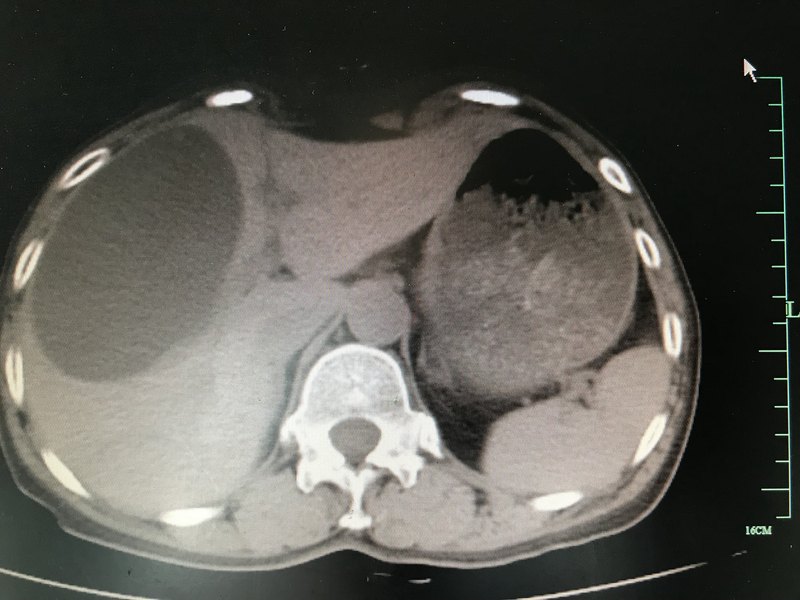

術(shù)前CT表現(xiàn) 另一患者的CT表現(xiàn) 囊腫開窗后的術(shù)中情況 帶蒂大網(wǎng)膜填塞囊腔避免術(shù)后復(fù)發(fā) 腹壁切口 術(shù)后復(fù)查囊腫消失,囊腔內(nèi)為填塞的網(wǎng)膜,肝臟體積較前增大

肝血管瘤是肝臟常見的良性腫瘤,隨著B超檢查的廣泛應(yīng)用,其檢出率逐漸增高。許多患者拿到檢查報告后都心有余悸,其實(shí)肝血管瘤并沒有多么可怕,因為絕大多數(shù)的肝血管瘤是不用治療干預(yù)的,那么哪些情況下的肝血管瘤需要進(jìn)一步治療呢?治療又采取哪種方式呢?肝血管瘤治療的指征主要有如下幾點(diǎn):1、不能排除肝惡性腫瘤可能者;2、生長在肝臟的特殊部位,如第二肝門、第三肝門,且隨訪逐年增大者;3、隨訪過程中增長迅速者;4、瘤體直徑5cm-10cm者且有癥狀者;5、瘤體直徑達(dá)到10cm者;6、瘤體破裂出血者;--其實(shí)肝血管瘤自發(fā)性破裂的可能性極?。。。「窝芰鲋委煹那疤崾窃\斷必須明確,不能單憑B超檢查結(jié)果確診是肝血管瘤,尤其是合并有慢性病毒性肝炎或肝硬化背景的患者,需要做進(jìn)一步的上腹部CT或MRI平掃+增強(qiáng)掃描檢查及腫瘤標(biāo)志物檢查排除肝臟惡性腫瘤可能?。。∧壳搬槍Ω窝芰龅闹委熤饕椒ㄓ校簜鹘y(tǒng)的開腹手術(shù)、腹腔鏡手術(shù)、介入栓塞治療、微波或射頻消融治療。目前主流的治療方式仍是外科手術(shù),目前治療現(xiàn)狀主要是治療過度或指征把握不嚴(yán)造成許多無需治療的肝血管瘤被誘導(dǎo)治療!傳統(tǒng)的開腹手術(shù)創(chuàng)傷大,恢復(fù)慢,但相對安全有效。隨著腹腔鏡技術(shù)的推廣應(yīng)用,腹腔鏡肝切除技術(shù)逐漸成熟,其創(chuàng)傷小,恢復(fù)快,但對腔鏡技術(shù)要求高,操作復(fù)雜。對符合治療指征的肝血管瘤除了瘤體破裂出血的急救處理外,其他情況下介入治療治療效果難以評價,存在栓塞不完全,復(fù)發(fā),破裂,感染等風(fēng)險,不作為常規(guī)推薦。肝血管瘤血供豐富,消融治療出血風(fēng)險大,不常規(guī)推薦。近日,我科團(tuán)隊成功實(shí)施了腹腔鏡下解剖性左肝外葉切除術(shù)治療左肝外葉巨大肝血管瘤,手術(shù)過程順利,術(shù)后患者恢復(fù)順利。手術(shù)相關(guān)鏈接:http://surgeon.dxy.cn/bbs/topic/36471869